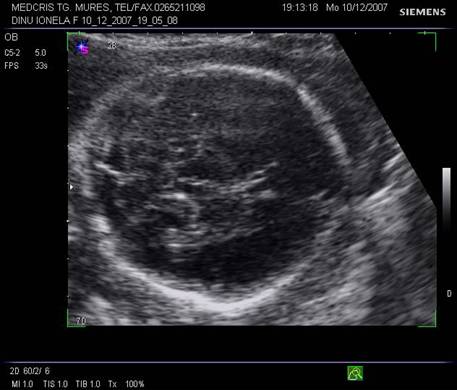

Capul

Craniul fetal poate fi explorat ecografic in 3 planuri de baza : transversal, sagital si cranial/frontal.[1,3,8,13,14]

In cursul trim II, bolta craniana apare ca bine definita, hiperecogena, elipsoidala. Suturile si fontanelele trebuie recunoscute ca fiziologice si nu trebuie confundate cu defecte structurale craniene.

Linia de mijloc hiperecogena frontoocipitala este formata anterior si posterior de falx cerebri si fisura interemisferica, central de septum pellucidum. La sfarsitul primului trimestru de sarcina, linia de mijloc hiperecogena este flancata la distanta de o pereche de ventriculi laterali, ce inconjoara plexurile choroide ecogene. Din saptamana a 15-a cresterea cortexului devine vizibila, la marginea ventriculilor laterali, ca o margine hipoecogena. Partea posterioara a ventriculilor laterali ramane ocupata de plexurile choroide, in timp ce coarnele anterioare contin doar fluid. Dupa saptamana 19-a ventriculii laterali au caractere constante pe tot parcursul sarcinii.[1,3,8,13,14]